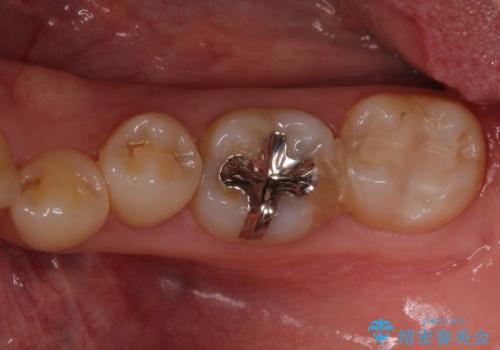

- 銀歯の周りの歯が欠けてしまい、気になるとのことで来院された患者様です。

痛みなどは特になく、診査をしたところ歯の神経に大きな問題はなかったのですが、レントゲン写真より神経に近くに迫るほど大きなむし歯があることが分かりました。

虫歯が歯髄腔(神経の部屋)に達している可能性が非常に高かったため、炎症を起こしている神経組織を部分的に切除し、歯根部分の神経組織を保存する治療法が望ましいと考えられました。

元々の銀歯も大きく装着されていたため、虫歯治療後はセラミッククラウンにて補綴することとしました。